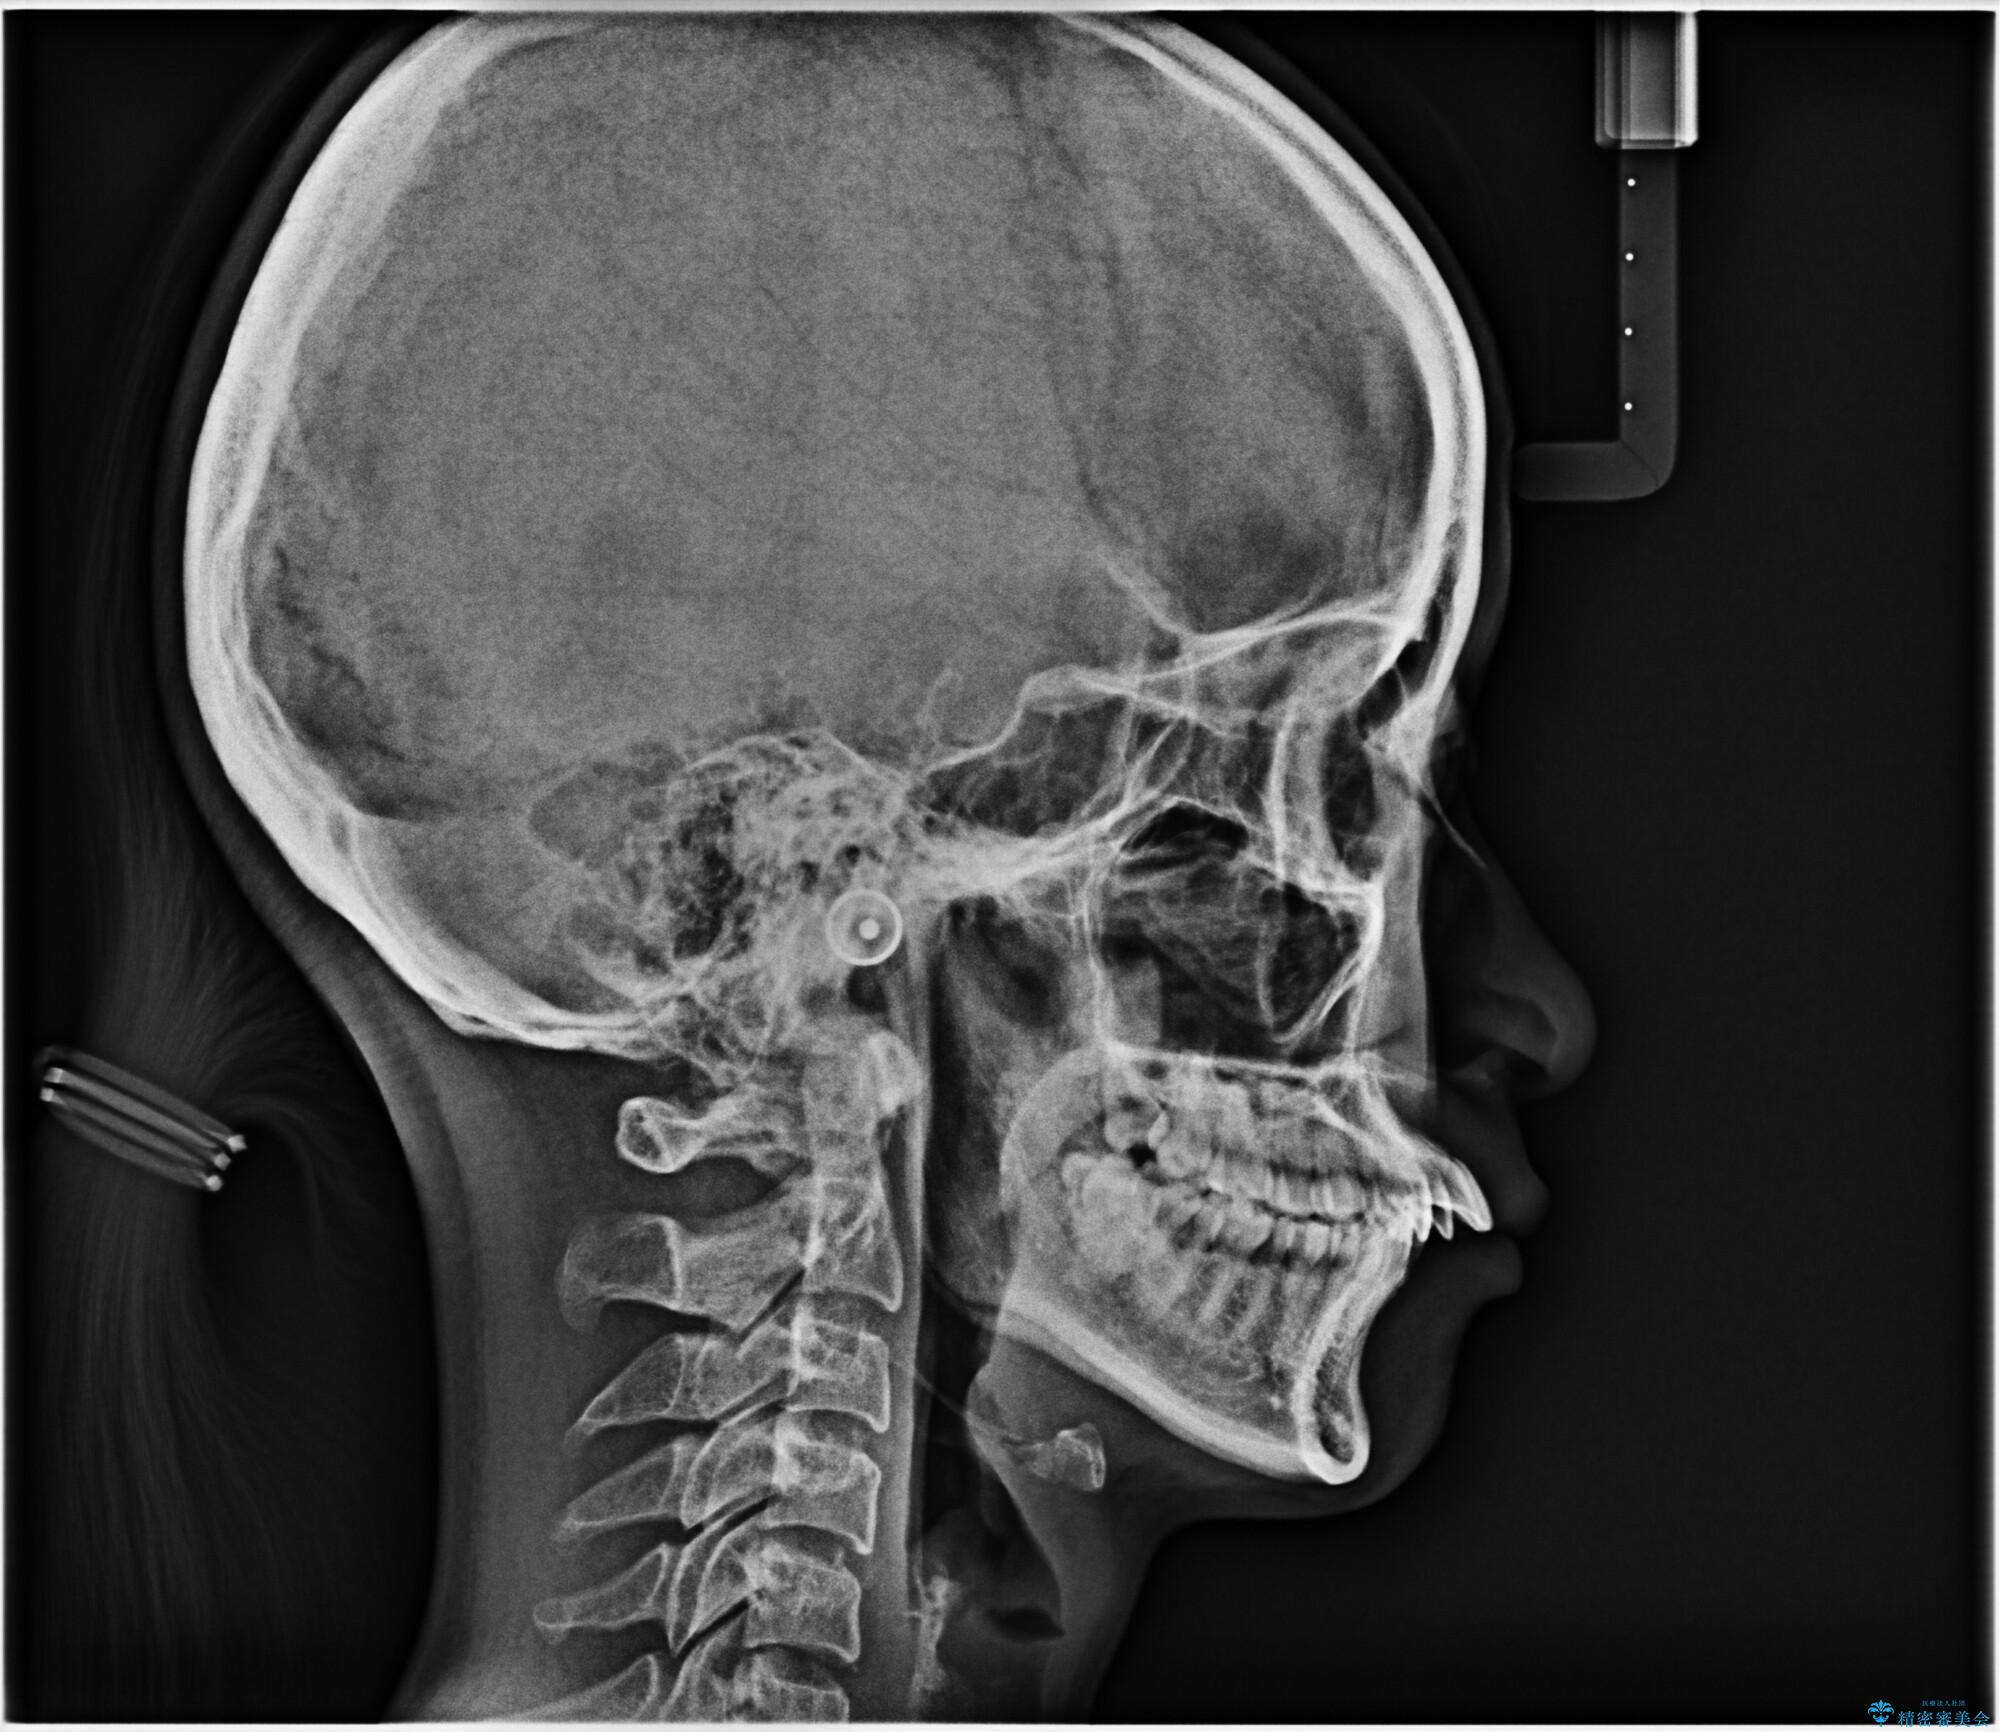

- 前歯が出ていることを主訴に来院されました。

下顎前歯が1本欠損していることもあり、前突はある程度残ることを説明し、インビザラインにて治療を行いました。

今回は抜歯矯正ではなく歯列弓の拡大とIPR、遠心移動を行って配列することができました。

下顎前歯が1本少ないため、上下の正中は合いません。